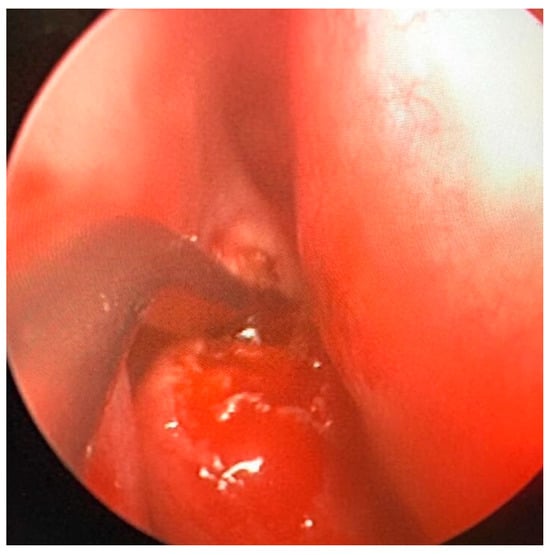

The patient had already performed a skull CT scan that showed an osteostructural alteration with a swollen appearance of the bone component of the right ethmoidal cells, with the encumbrance of the homolateral nasal fossa and the probable involvement also of the homolateral orbital walls; the neoformation was 24 × 43 × 38 mm (Figure 1).

Figure 1. Pre-operative CT Image of Patient 1. (A) An axial cut; (B) a coronal cut. In both, the extension of the lesion into the ethmoidal region is evident.